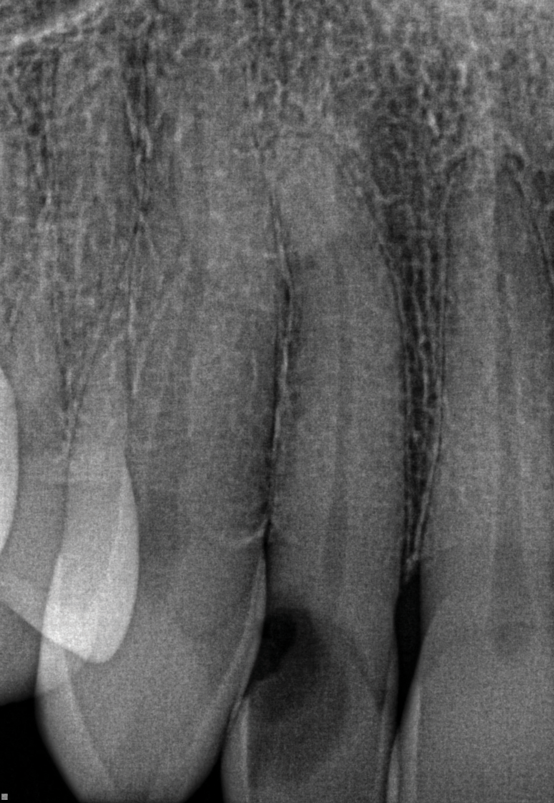

Other common risks associated with post placement include the occurrence of root fracture, perforation, and apical leakage as well as the development of caries (Figure 1 through Figure 3).9 How the post space is prepared significantly affects the ability of the root canal filling material to create a seal.11 Apical leakage increases in correlation with the amount of gutta percha removed from an endodontically treated tooth, increasing the risk of reinfection.11 The risks of fracture and perforation must also be seriously considered. After the performance of endodontic treatment alone, furcation-side dentin thickness in the distal roots of mandibular molars has been shown to be less than 1 mm in more than 80% of teeth.12 After preparation of the post space, the remaining dentin thickness in the buccal roots of premolars has been shown to be often less than 1 mm.13 The remaining thickness of the root dentin after endodontic and post placement procedures is the factor most highly correlated with future resistance against root fractures.13 These anatomic studies underscore the need for judicious preparation, and the risks of post placement underscore the need for careful case selection.

(2.) A radiograph of a root fracture associated with a threaded post, cone-beam computed tomography views of a perforation associated with a post, and a radiograph demonstrating evidence of apical leakage associated with posts, respectively.

Figure 2